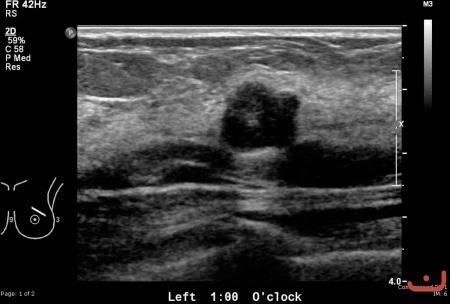

Case 66-D1

Benign solid mass

Date

Friday, 22 May 2015

File size of the original image

86.30 KB (451 x 305 px)